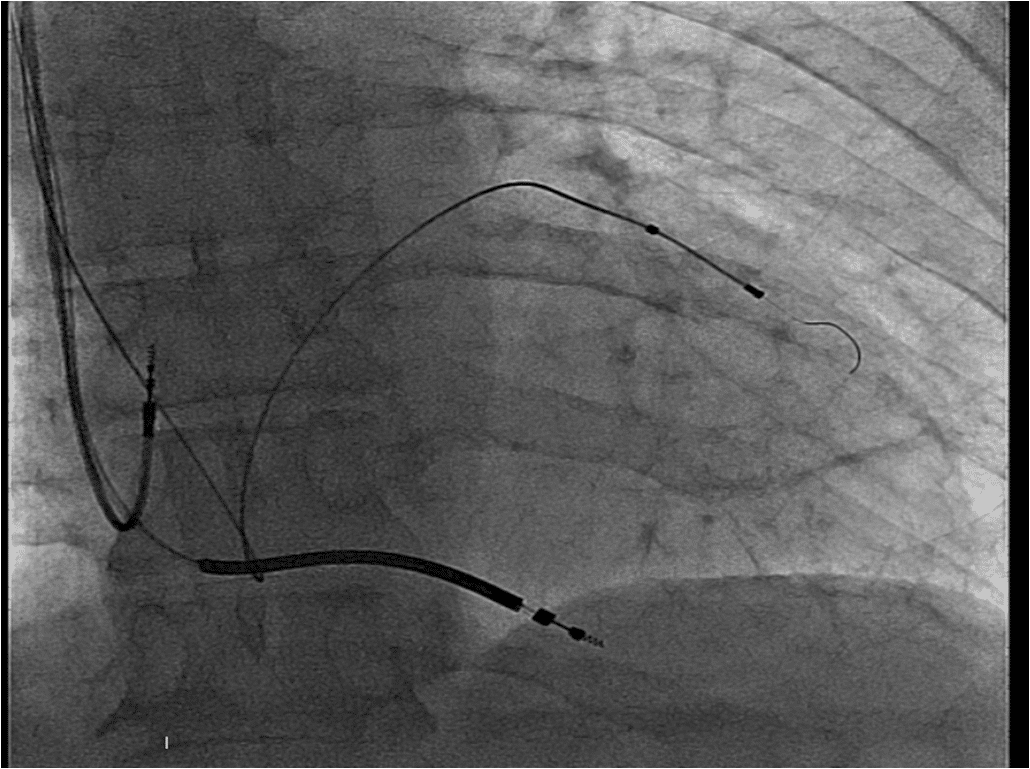

A 75 years old man with an ejection fraction of 35%, QRS duration 155 miliseconds and LBBB morphology on surface electrocardiogram was shedduled for CRT-D device implantation. Venography was performed as a part of our routine practice in order to explore the patency of the subclavian vein. After being sure about the patency of the vein, a pocket was created in the left pectoral region. The vein was canulated but the attempt to advance the guidewire has aborted. The tip of the guidewire fastened on a steep angle through the course of the vein. The venography was looked on again. Presence of a regressed innominate vein in a tapered aspect was noticed as well as a downward flow on the left side of the view . The patient had a PLVCS. Venography using the right antecubital vein showed the presence of a patent right SVC. A new pocket was created on the right pectoral region. Atrial, right ventricular and left ventricular leads were implanted using the right axillary vein puncture (Figure 1, 2). The procedure was quite straightforward and carried out succesfully (Figure 3).